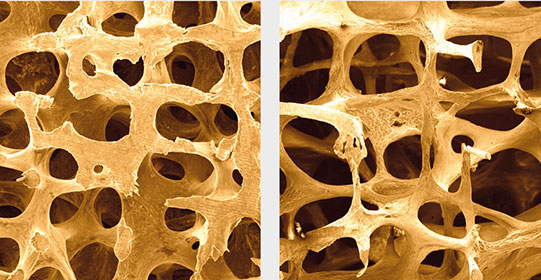

Professor Dr. med. Ulrich Liener ist Ärztlicher Direktor der Klinik für Orthopädie, Unfallchirurgie und Sporttraumatologie des Marienhospitals. Eines seiner Spezialgebiete ist die Alterstraumatologie, bei der es um Verletzungen und Knochenbrüche im Alter geht. Hier spielt insbesondere die Osteoporose (Knochenschwund) eine große Rolle. Denn diese führt letztlich zu den vielen Knochenbrüchen älterer Menschen bereits bei leichten Stürzen.

„Weil die Bevölkerung immer älter wird und Knochenschwund vor allem im Alter auftritt, ist Osteoporose heute eine Volkskrankheit“, so Ulrich Liener. „Wissenschaftler weltweit stellen sich die Frage, wie man Osteoporose im Alter verhindern kann und wie man eine bereits vorhandene Osteoporose optimal behandelt“, sagt Professor Liener. Daher werden jedes Jahr hunderte entsprechender Studien durchgeführt. Die besten werden in medizinischen Fachjournalen veröffentlicht.